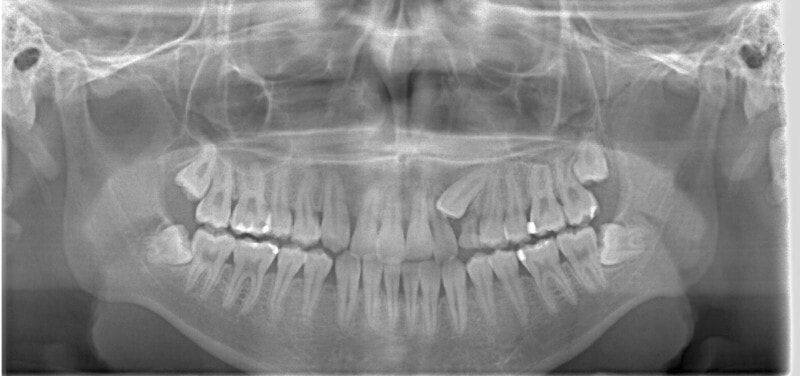

治療前

やはり統計通り、左上3番の埋伏です。

左上2番の歯根吸収が認められますが、保存不可能なレベルではありません。

成人の反対咬合なので、少し顎関節にダメージはありますが、重症ではありません。